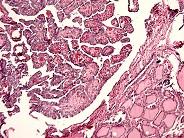

问题 关于甲状腺乳头状癌,下列哪项不正确 ( )

选项 A、约占成人甲状腺癌的大多数 B、多中心者占大多数 C、较早出现颈淋巴结转移 D、老年人占大多数 E、女性占大多数

答案 D